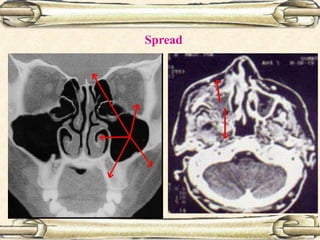

Spread

Medial spread:

Unilateral nasal obstruction

Unilateral purulent nasal

discharge

Epistaxis

Unilateral, friable, nasal mass

Anterior spread:

Cheek swelling

Invasion of facial skin

Superior spread:

Proptosis

Diplopia

Ocular pain

Posterior spread:

Pterygoid muscle involvement  trismus

Intracranial spread via:

Ethmoids, cribriform plate or foramen lacerum